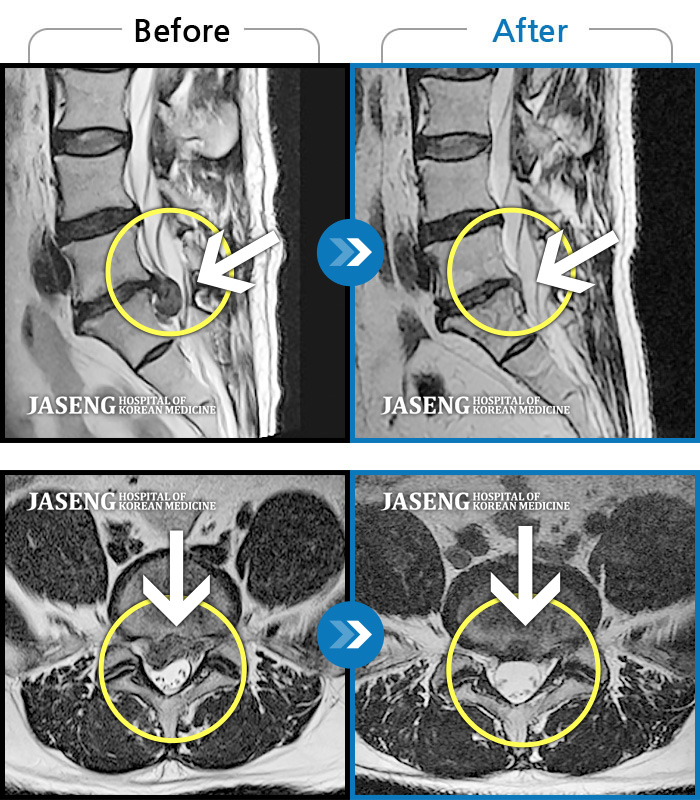

Before

After

환자에게 사전 동의를 받아 동일 조건에서 촬영되었습니다.

개인에 따라 치료 후 부작용이 발생할 수 있으니 의료진과 상담 후 치료를 진행하시기 바랍니다.

허리디스크로 인한 양측 허리 통증